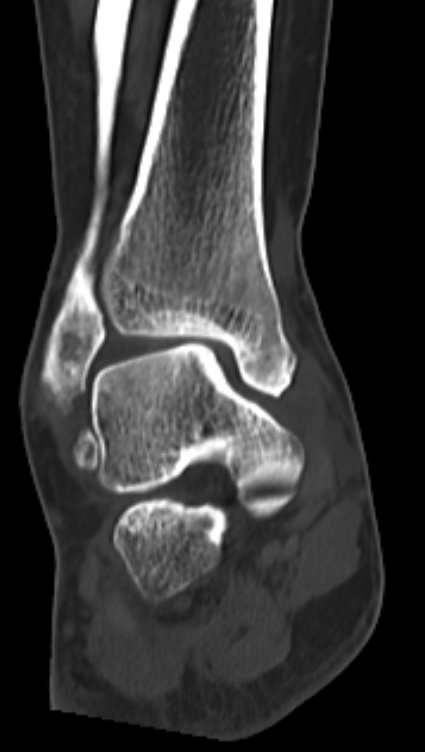

术前CT

针对这种局部病变,团队用了3D打印部分距骨置换术。

这种手术不用大动,只换病变的那部分距骨,尽量保住健康的关节组织,创伤小,术后恢复起来也能快一点。